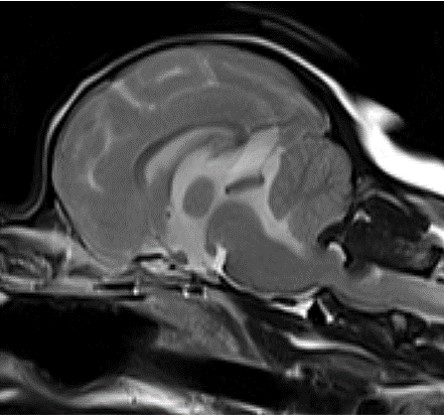

MRI의 경우 특히 뇌와 척수의 신경계와 같은 연부조직의 영상화에 특화되어 있어 다른 영상 기법보다 뛰어난 해상도를 나타냅니다.

- 뇌수두증

- 뇌종양

- 뇌수막염

- 두경접합부 질환

뇌수두중 -

후두골이형성,키아리 기형 -